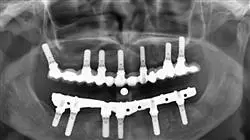

Область челюстно-лицевой имплантации постоянно развивается благодаря исследованиям и разработкам по методикам и материалам. Будущее челюстно-лицевой имплантации базируется на трех фундаментальных направлениях: импланты с биодеградируемыми покрытиями, использование технологий

в имплантологии и стволовые клетки. Во всех этих направлениях качество и точность являются основополагающими для их успешной реализации.

Прогресс был достигнут также за счет подхода к опорным тканям, ускорения остеоинтеграции с помощью биоактивных поверхностей и используемых клинических протоколов. Этот прогресс, несомненно, стимулирует стремление специалистов к постоянному повышению квалификации в данной области. В ответ на эту потребность был разработан Курс профессиональной подготовки в области челюстно-лицевой имплантации, который преподается специализированной командой преподавателей, подготовивших учебные материалы, обеспечивающие специалистов самыми современными знаниями в области диагностики у пациентов с ограниченными возможностями здоровья, восстановления как руководства для осуществления комплексного имплантационного лечения, материалов для имплантационных протезов и планирования имплантации.